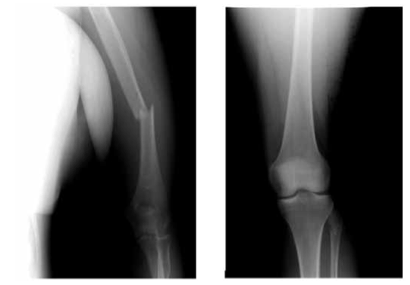

Больной Ж., 22 г. Сочетанная травма. Повреждение левого купола диафрагмы. Картина дислокации органов брюшной полости в левую плевральную полость. Закрытый перелом плечевой кости, закрытый перелом малоберцовой кости. Тяжесть повреждений по шкале оценки ВПХ П. (МТ) — 9,2 балла, ВПХ (СП) — 27

При сочетанной травме тактические подходы к лечению пострадавших необходимо проводить по принципу «Damage control» (7). Устранение повреждений диафрагмы при сочетанной травме является приоритетным. В данном клиническом случае на первом этапе произведена ликвидация разрыва диафрагмы путем ушивания лапаротомным доступом, дренирование плевральной полости. Вторым этапом проведен интрамедуллярный остеосинтез перелома плечевой кости.